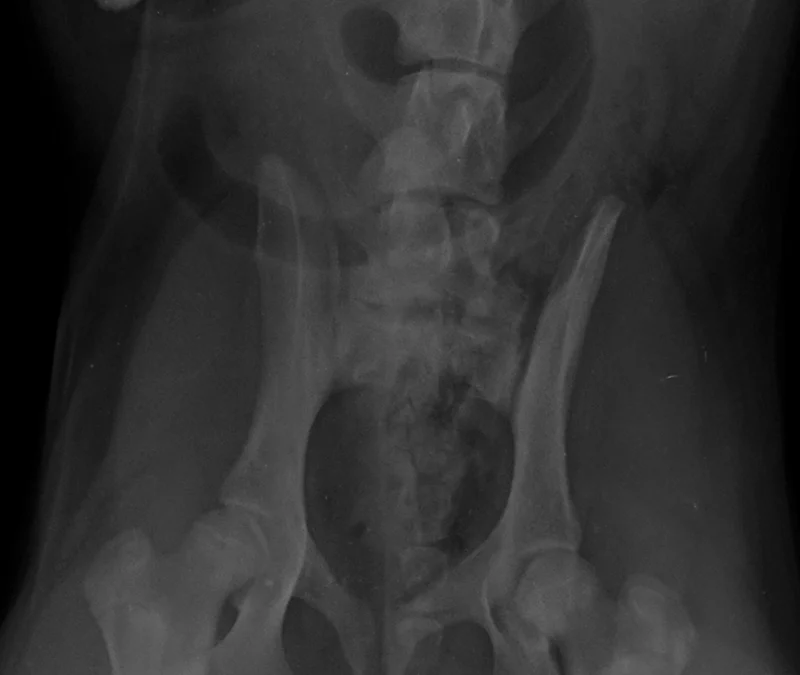

Timbertown-Vet-Swallowing-Rocks-Imaging